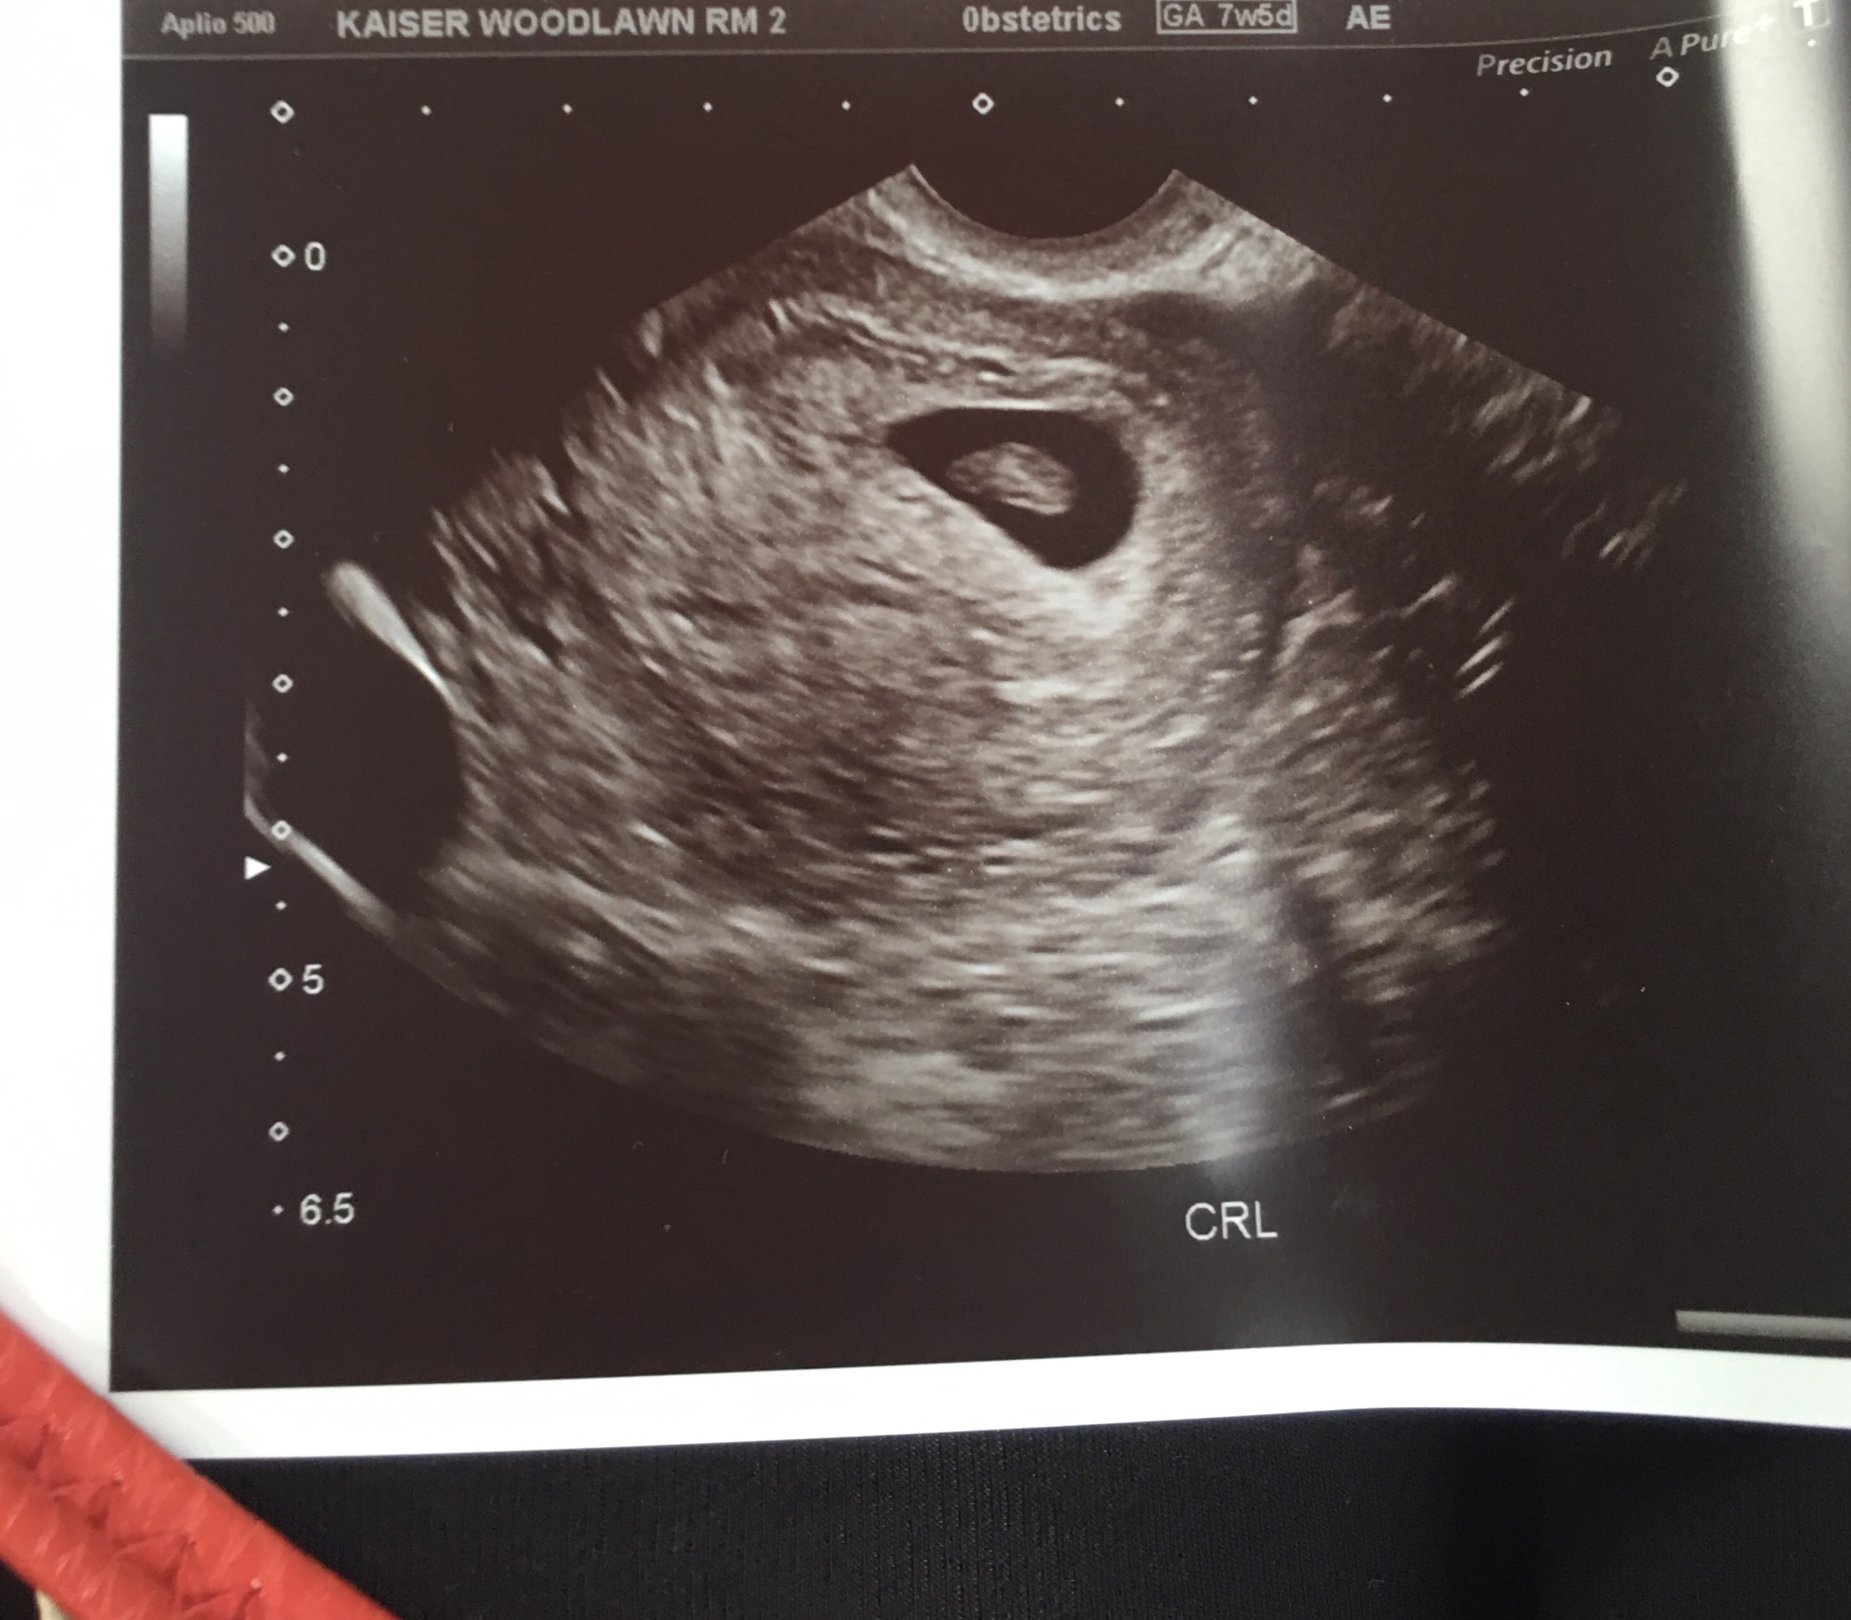

got our ultrasound but the technician wouldn't give is any info on heartbeat and size of fetus. But she did show is the heartbeat. Going to see the doc on Monday for all the juicy details. Here is the ultrasound, according to my last period it should be 7 weeks and 1 day in this pic. Kind of worried the tech didn't want to give us any information